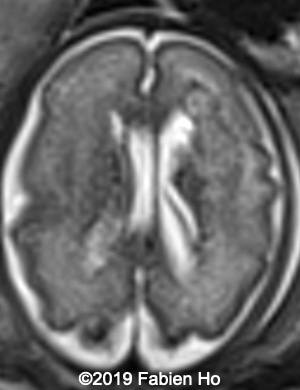

Images 1-3: in the left frontal lobe, hyperechoic with hypoechoic center lesion within the deep and periventricular white matter. Interestingly, this lesion has no mass effect on the lateral ventricle, and it has smooth margins.

Images 4-11, fetal brain MRI at 28 weeks: the left frontal lesion hence shows DWI hyperintensity, with T2* and T1 peripheral hyperintensity: ischemia with peripheral subacute hemorrhage. Note also that there is an associated blood clot in the left lateral ventricle. There is no obvious mass effect, nor peripheral edema. All these findin>gs are very suggestive of a clastic lesion.

Axial T2w

4

5